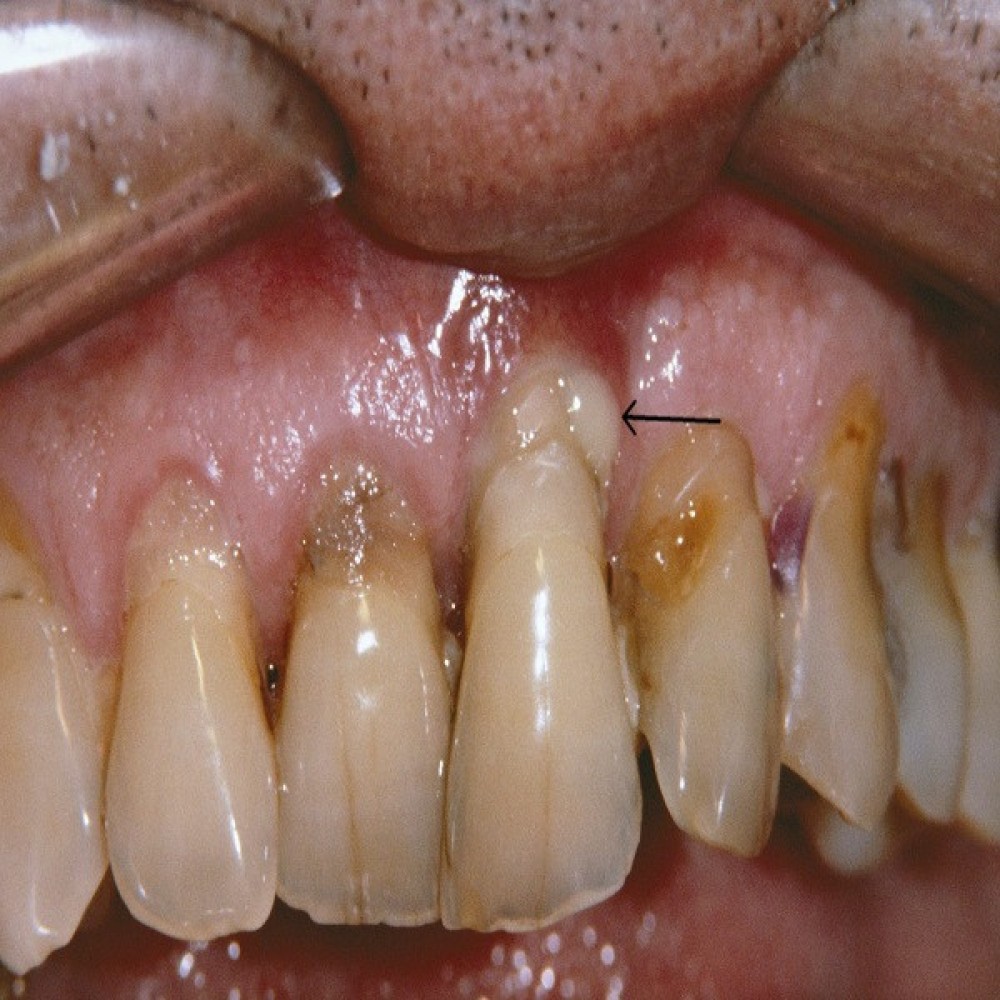

Periodontitis (Advanced Stage)

Symptoms: Swollen, bleeding gums; receding gums; bad breath (halitosis); loose teeth; gum abscesses; and changes in how teeth fit together when you bite.